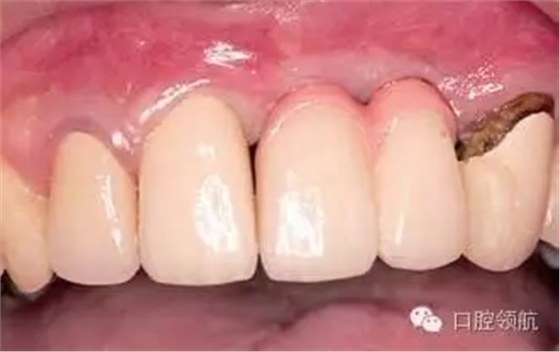

可以選擇在(右上第1、2顆牙) 部位的唇側進行結締組織移植來獲得牙齦組織美學形態(tài)連續(xù)性的恢復的外科方式。在本病例中,因為患者不是露齦笑的類型,所以選擇了用修復的辦法提高美學效果,在金屬基底冠上,使用牙齦瓷,來恢復牙齦形態(tài)對稱性(圖2、圖3)。

圖2 戴入上部基臺的狀態(tài)。

圖3 戴入有牙齦瓷的金屬基底烤瓷冠,(右上第3顆牙) 是不良修復體,計劃在(右上第1、2顆牙)種植區(qū)周圍的軟組織穩(wěn)定后,再對(右上第3顆牙) 進行重新修復。